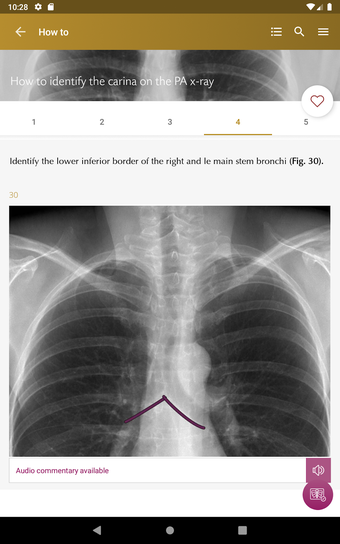

Radioloji'yi Keşfet: Göğüs Röntgeni Yorumlama, göğüs röntgeninin yorumlanmasının anlaşılmasını artırmak için tasarlanmış bir eğitim uygulamasıdır ve doktorlar, tıp öğrencileri ve radyologlar tarafından kullanılması amaçlanmaktadır. Uygulama, en küçük detayları görüntülemek için yakınlaştırılabilecek yüksek kaliteli görüntüler ve her bulgunun önemini anlamanıza yardımcı olacak bir sesli yorum içerir.

Ayrıca, uygulama bir hastanın göğüs röntgenini incelemeleri sırasında başvurabilecekleri bir dizi nasıl yapılır içerir. Uygulamadaki nasıl yapılır adımlarını takip ederek, kullanıcılar birçok farklı bulguyu doğru bir şekilde tanımlayabilecekler ve her birini bir hastalığın teşhisi için nasıl doğru bir şekilde kullanacaklarını öğrenebileceklerdir.